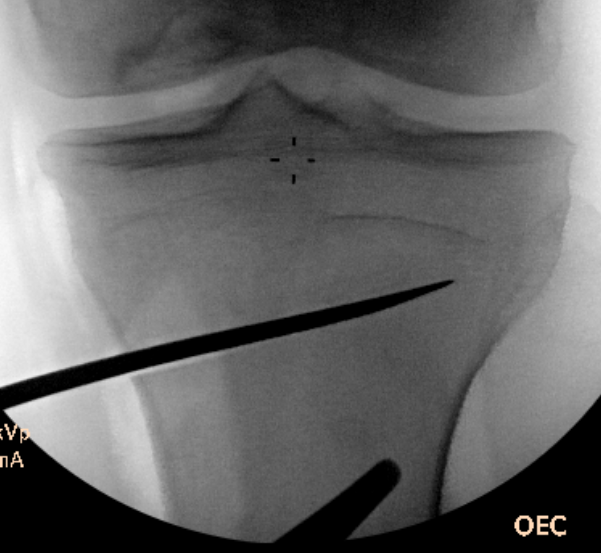

Check correct alignment with drop rod

- goal lateral tibial spine

- Fujisawa point / 62% of the tibial plateau / lateral tibial spine